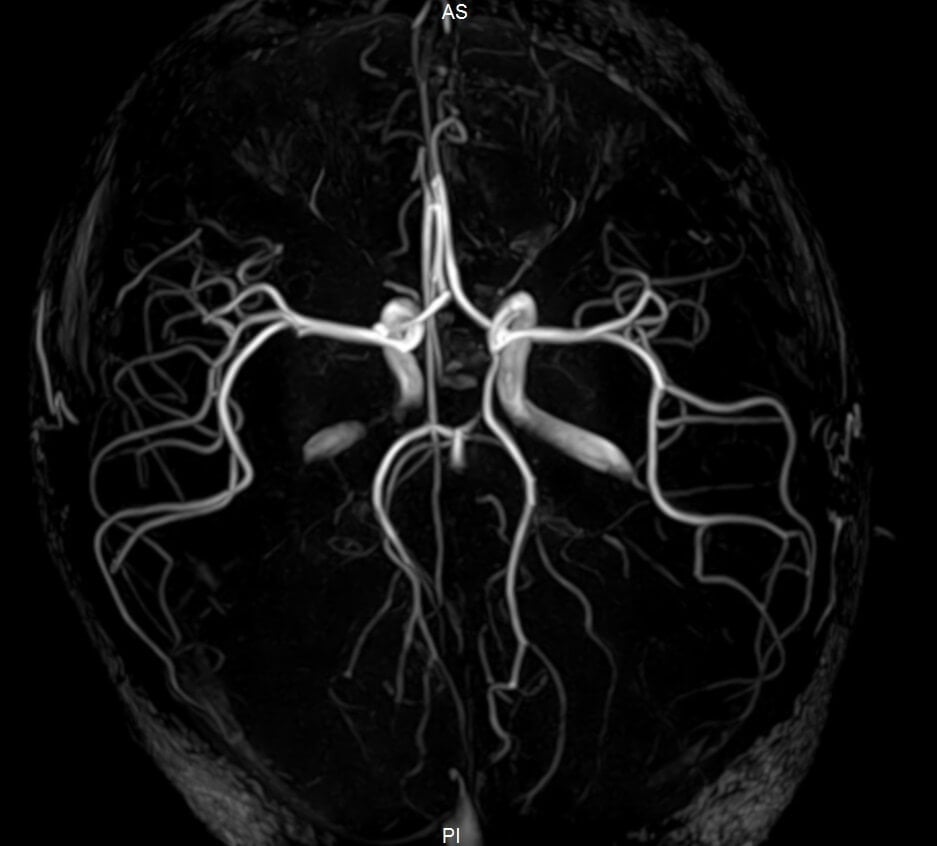

From www.pinterest.com

(anatomia.repost) on Instagram “Repost cmusom ・・・ 7.0 Tesla What Is A Mri Angiography It looks just at the body’s blood vessels. Magnetic resonance angiography (mra) encompasses several imaging techniques based on magnetic resonance imaging (mri) developed for studying the. A regular angiogram requires inserting a thin tube. Magnetic resonance angiography (mra) is an imaging test that shows your blood vessels and blood flow. Magnetic resonance angiography (mra) is a type of mri. Magnetic. What Is A Mri Angiography.